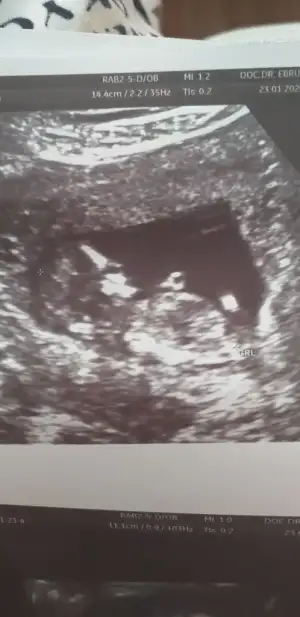

Merhaba arkadaşımın bebeği için cinsiyet yorumlarmısınız ☺️☺️

Eklentiler

• F17F74DB-0A55-4017-AE3F-ACD7B369930D.webp

F17F74DB-0A55-4017-AE3F-ACD7B369930D.webp

21,2 KB · Görüntüleme: 47